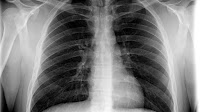

Influenza-like illness is a nonspecific respiratory illness characterized by fever, fatigue, cough, and other symptoms that stop within a few days. Most cases of ILI are caused not by influenza but by other viruses (e.g., rhinoviruses, coronaviruses, human respiratory syncytial virus, adenoviruses, and human parainfluenza viruses). Less common causes of ILI include bacteria such as Legionella, Chlamydia pneumoniae, Mycoplasma pneumoniae, and Streptococcus pneumoniae. Influenza, RSV, and certain bacterial infections are particularly important causes of ILI because these infections can lead to serious complications requiring hospitalization. Physicians who examine persons with ILI can use a combination of epidemiologic and clinical data (information about recent other patients and the individual patient) and, if necessary, laboratory and radiographic tests to determine the cause of the ILI.